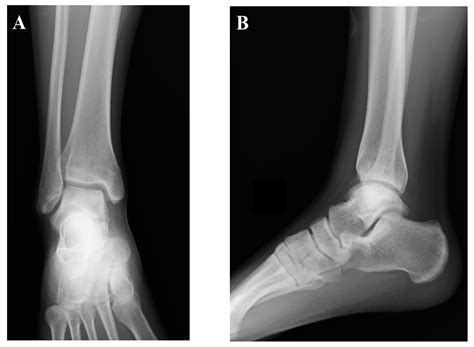

Talus Bone Anatomy